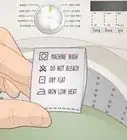

3Wear comfortable clothes and shoes. Dress comfortably for an X-ray because you will most likely be removing your outfit prior to the exam and/or sitting and waiting for an extended period of time.[4]

- Wear loose clothing that you can easily remove, such as a button-up shirt and even a front-clasping bra for women.

4Remove all jewelry, glasses, and metal objects. It is best to leave your jewelry at home as you may need to remove it for the exam. If you wear glasses, you may need to remove these as well.